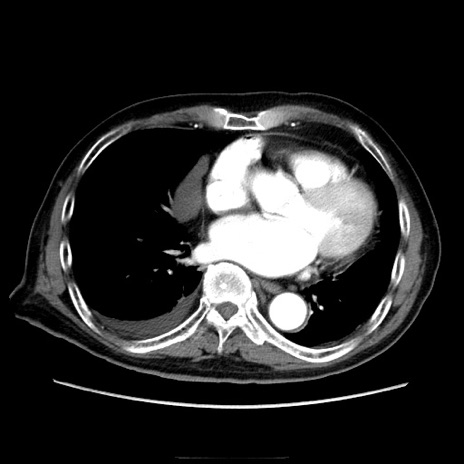

冠状断像